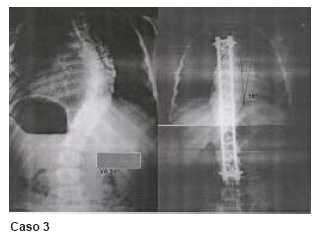

En el caso 3, que corresponde a una curva tóraco-lumbar, se parte de un valor angular de 58º y con descenso a 22º en el bending, obteniendo corrección final quirúrgica de 22º.

Los casos 14 y 15 corresponden a curvas torácica dextroconvexas en las que se parte de un valor angular de 50º con descenso a 25º en el bending, obteniendo corrección quirúrgica final a 15º en el caso 14 y partiendo de una curva de 70º con descenso a 22º en el bending, se obtiene una corrección final de 10º.